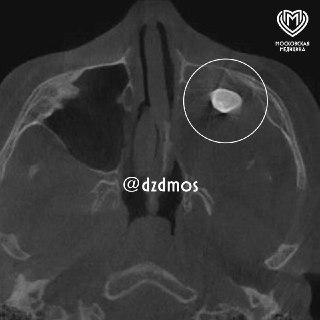

В Москве у 15-летнего подростка в носу неожиданно пророс зуб.

Мальчик обратился к врачам с жалобами на заложенность носа и асимметрию лица. В гайморовой пазухе был найден сформированный зуб. После консультации в Филатовской детской больнице диагноз подтвердился — тератома, опухоль, содержащая различные ткани, включая зубы. Хирурги успешно удалили образование, и теперь парень снова дышит свободно, асимметрия лица исчезает.